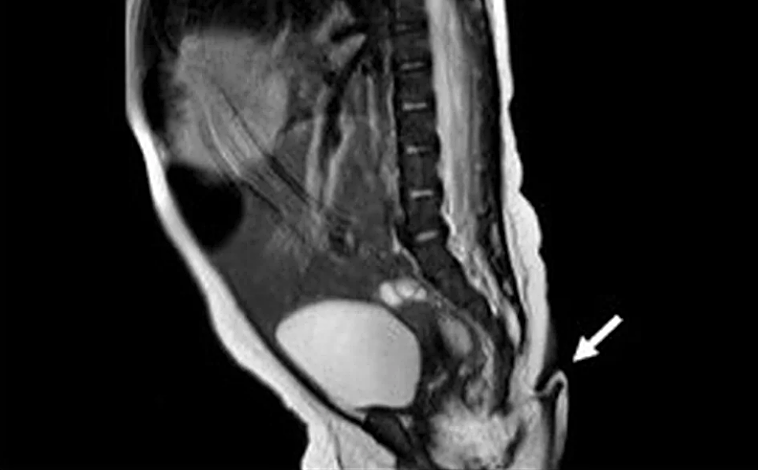

Fue en el momento del nacimiento, durante la cesárea, cuando los médicos advirtieron de este apéndice que medía 5,7 cm de largo y entre 3 y 5 milímetros de diámetro.

De forma inmediata, se procedió a estudiar la cola, que si bien no hacía movimientos espontáneos, sí experimentaba pequeños movimientos leves sin producir dolor. Los médicos confirmaron que tenía conexiones nerviosas, puesto que al pinchar con una aguja se produjo rápidamente el llanto del recién nacido.

Entre las diferentes pruebas comprobaron también que no había huesos en su interior ni ningún tipo de malformaciones renales, ni del tracto urinario y tampoco irregularidades que afectaran a la médula espinal o el cerebro, por lo que la pequeña era perfectamente sana.

La operación, en cambio, tuvo que esperar. Al cumplir los dos meses y comprobar que la evolución de la niña era buena, procedieron a extirpar la cola, que durante ese tiempo había crecido 0,8 centímetros. Los análisis posteriores revelaron que la muestra contenía tejido blando, incluyendo tejido fibroadiposo, estructuras vasculares y haces nerviosos, cubiertos por piel, sin alteraciones histopatológicas.